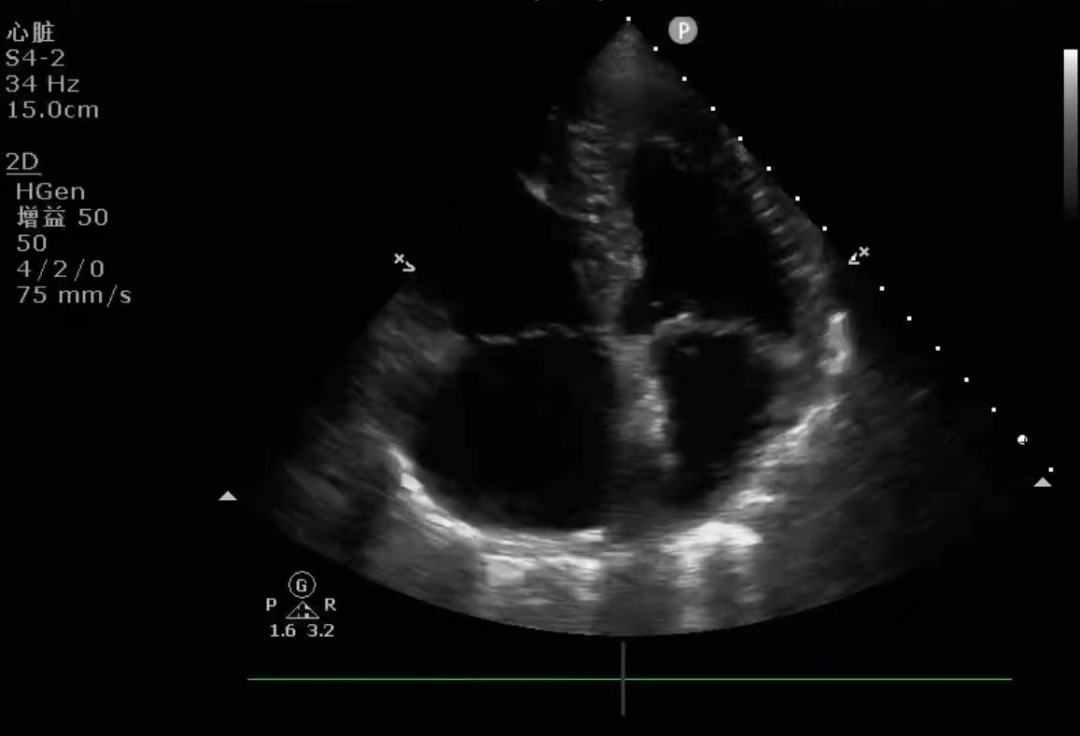

▲上图为ICU邓石荣科主任正在给一位急性心力衰竭患者进行心脏超声检查

(心尖四腔心切面)